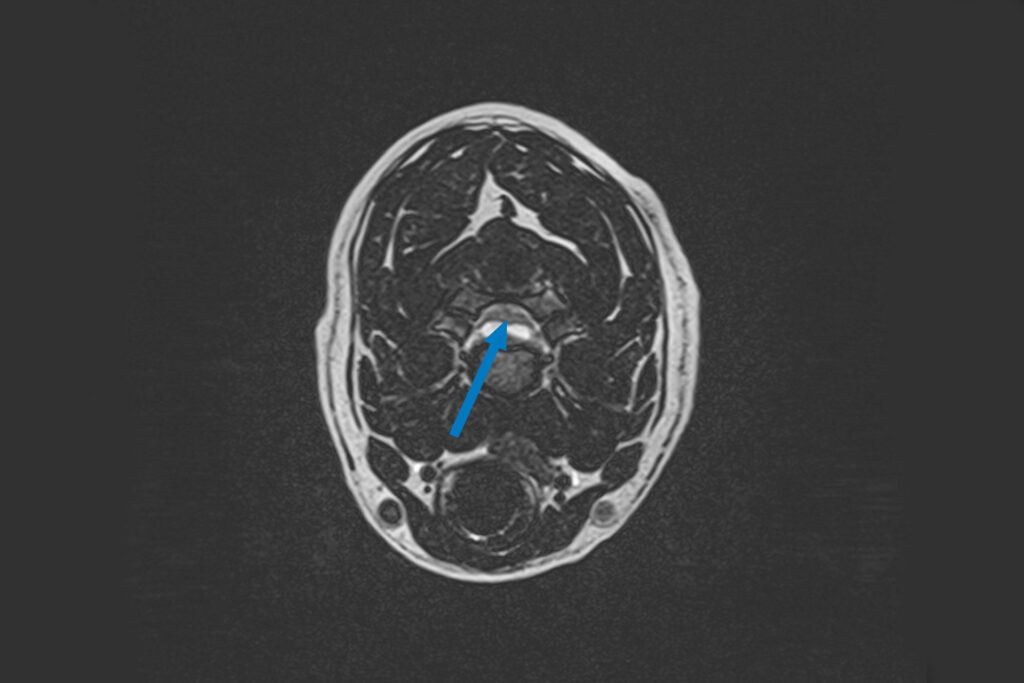

Our 1.5T MRI produces excellent contrast between various soft tissue structures in any plane of the body and is the gold standard for spinal imaging. In this instance, it was needed to visualise all the discs in Bryn’s neck, his spinal cord and nerve roots to identify what exactly was stopping the signals from his brain reaching his legs and where that was located. MRI revealed a hydrated disc extrusion at the level of C3-C4, which was compressing the spinal cord and starting to affect the nerves that control his breathing.